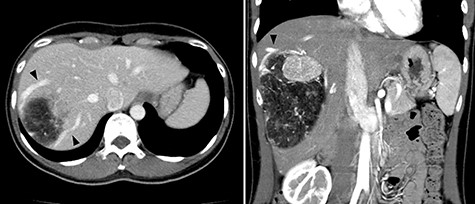

A 45-year-old woman was referred to our hospital with a huge liver tumor, which had been diagnosed as HAML 5 years previously when it was 12 cm in diameter (Fig. 1). Periodic follow-up with ultrasound and magnetic resonance imaging after the initial diagnosis had shown a progressive increase in the size of the tumor, and by the time of referral it measured 20 × 14 cm and had become symptomatic. On admission, enhanced computed tomography revealed a very large, well-defined, mixed-density mass occupying the entire right lobe of the liver (Fig. 2). Angiography showed dilated and tortuous vessel inside the tumor, and a drainage vein from the tumor to the right hepatic vein was visualized in the early phase (Fig. 3).

Abdominal CT on admission; the tumor had enlarged, occupying the entire right lobe of the liver, and measuring 200 × 140 × 120 mm.